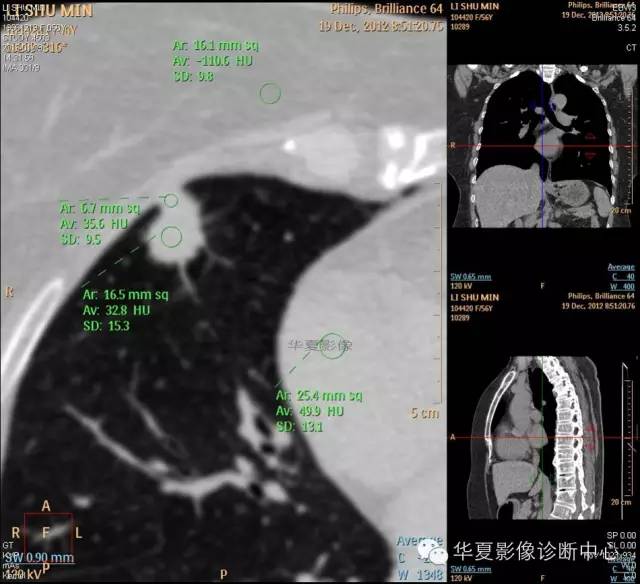

1.右肺上叶:肺组织1块,大小13×4×7cm。切面棕红色。2.右肺上叶肿物:灰白色组织一块,大小3×1×1.5cm。切面灰白色。3.右肺中叶结节:灰白色绿豆大组织1块。4.淋巴结:灰黑色绿豆大组织1块。

检查结论:

(右)肺中分化鳞状细胞癌。浸及胸膜。支气管残端切净。淋巴结未见癌转移(0/10)。